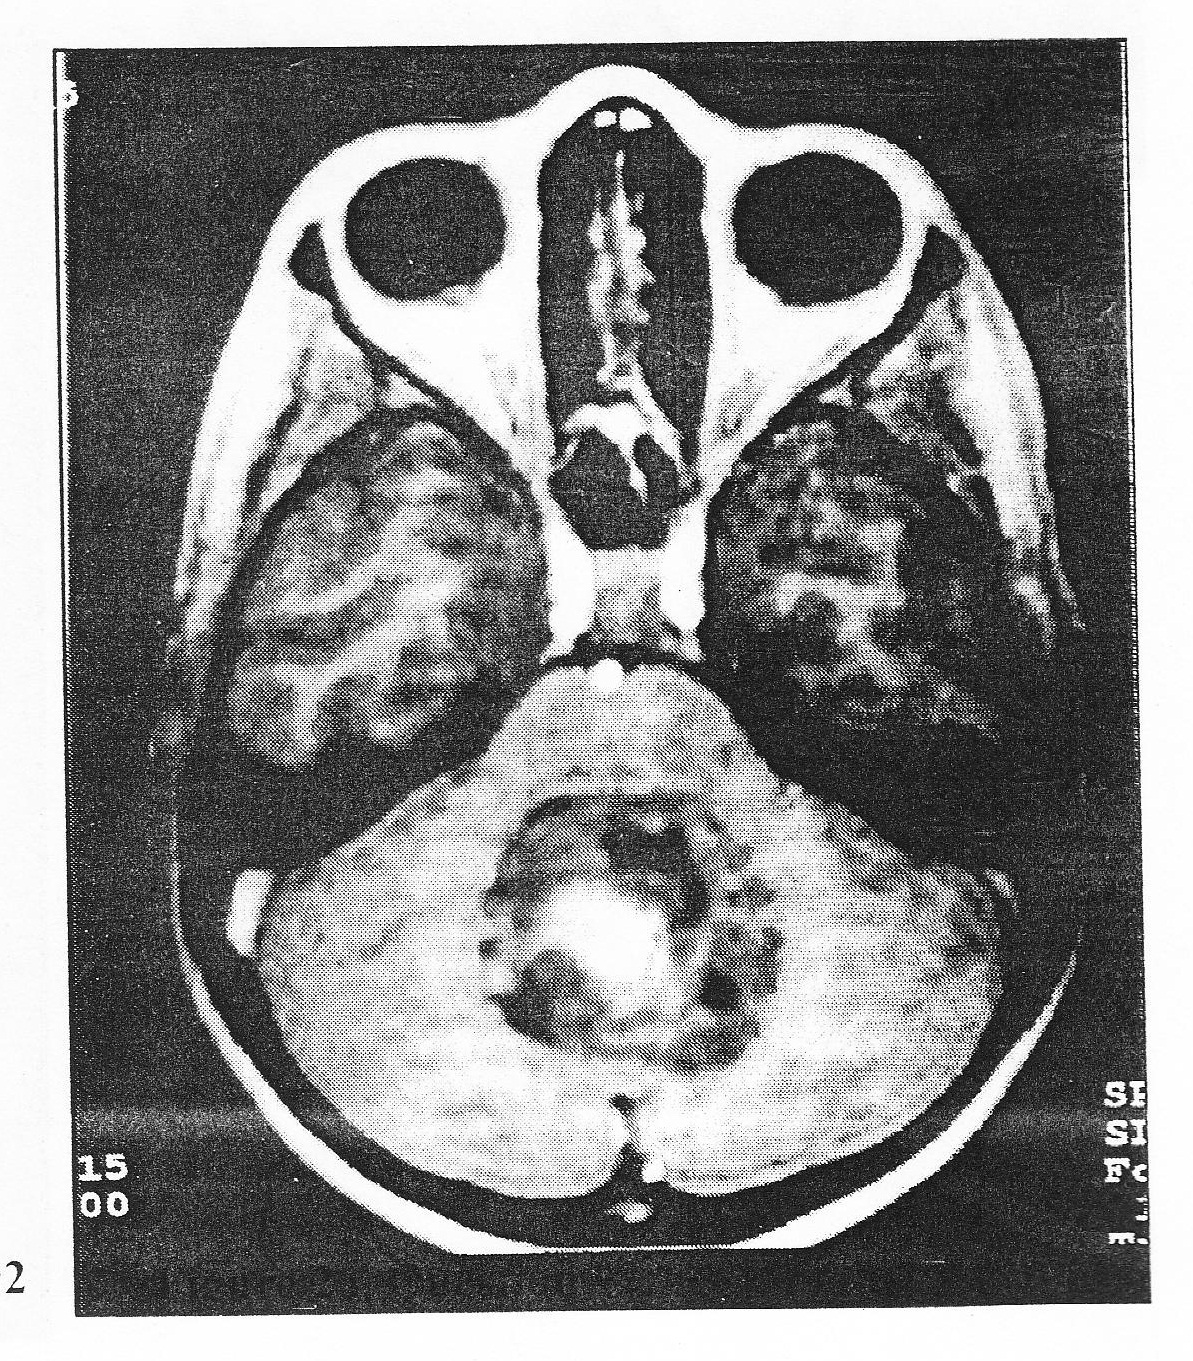

A 36-year-old non belted male driver was involved in a head on motor vehicle accident. On arrival in the emergency room, his pupillary, corneal, and gag reflexes were present and he flexed briskly to pain and has a Glasgow Coma Scale score of 5. His blood presure is 110/70 mmHg with a pulse of 100. An open comminuted femur fracture was apparent. A CT demonstrates open peri-mesencephalic cisterns with biofrontal contusions, with no extra-axial hematoma. This patient is admitted to the intensive care unit after ventriculostomy placement and a three hour open reduction and internal fixation procedure for femur fracture. Twelve hours later, his ICP climbs to 25 mmHg with mean arterial pressure of 75 mm Hg and cerebral perfusion pressure of 50 mmHg. His serum sodium is 146 mEq/dL and his hemoglobin is 9.5 g/dl, platelets are 1,900,000, and his prothrombin time is 13 second 97. Which of the following is the MOST LIKELY cause for the elevation in his ICP?

A. delayed extra-axial hematoma

B. diffuse cerebral edema due to axonal injury

C. volume overload

D. evolution of contusion to intracerebral hematoma